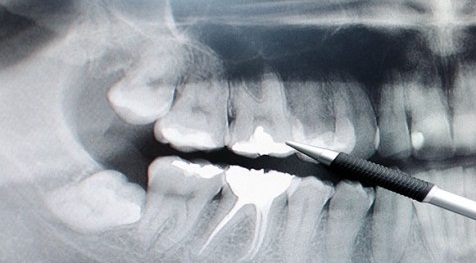

يُعاني مرضى السكري من آلام في أسنانهم مرتبطة بالتهابات الأوعية الدموية للب الأسنان وأحيانا قد يموت لب السن مما يتسبب بتغير لونه وظهوره بشكل قاتم كما تزداد حساسية الأسنان ويشعر مريض السكري بالألم عند الضغط عليها.

تؤثر الاصابة بالسكري تأثيرا شديدا على أنسجة اللثة فتتورم وتتضخم لأبسط الأسباب أو من تلقاء نفسها نتيجة لضعف أوعيتها الدموية بالالتهابات الحادة وتتقرح فتتكون الجيوب اللثوية العميقة ومع مرور الزمن يحدث امتصاص في العظم المحيط بالأسنان مما يتطلب خلعها .